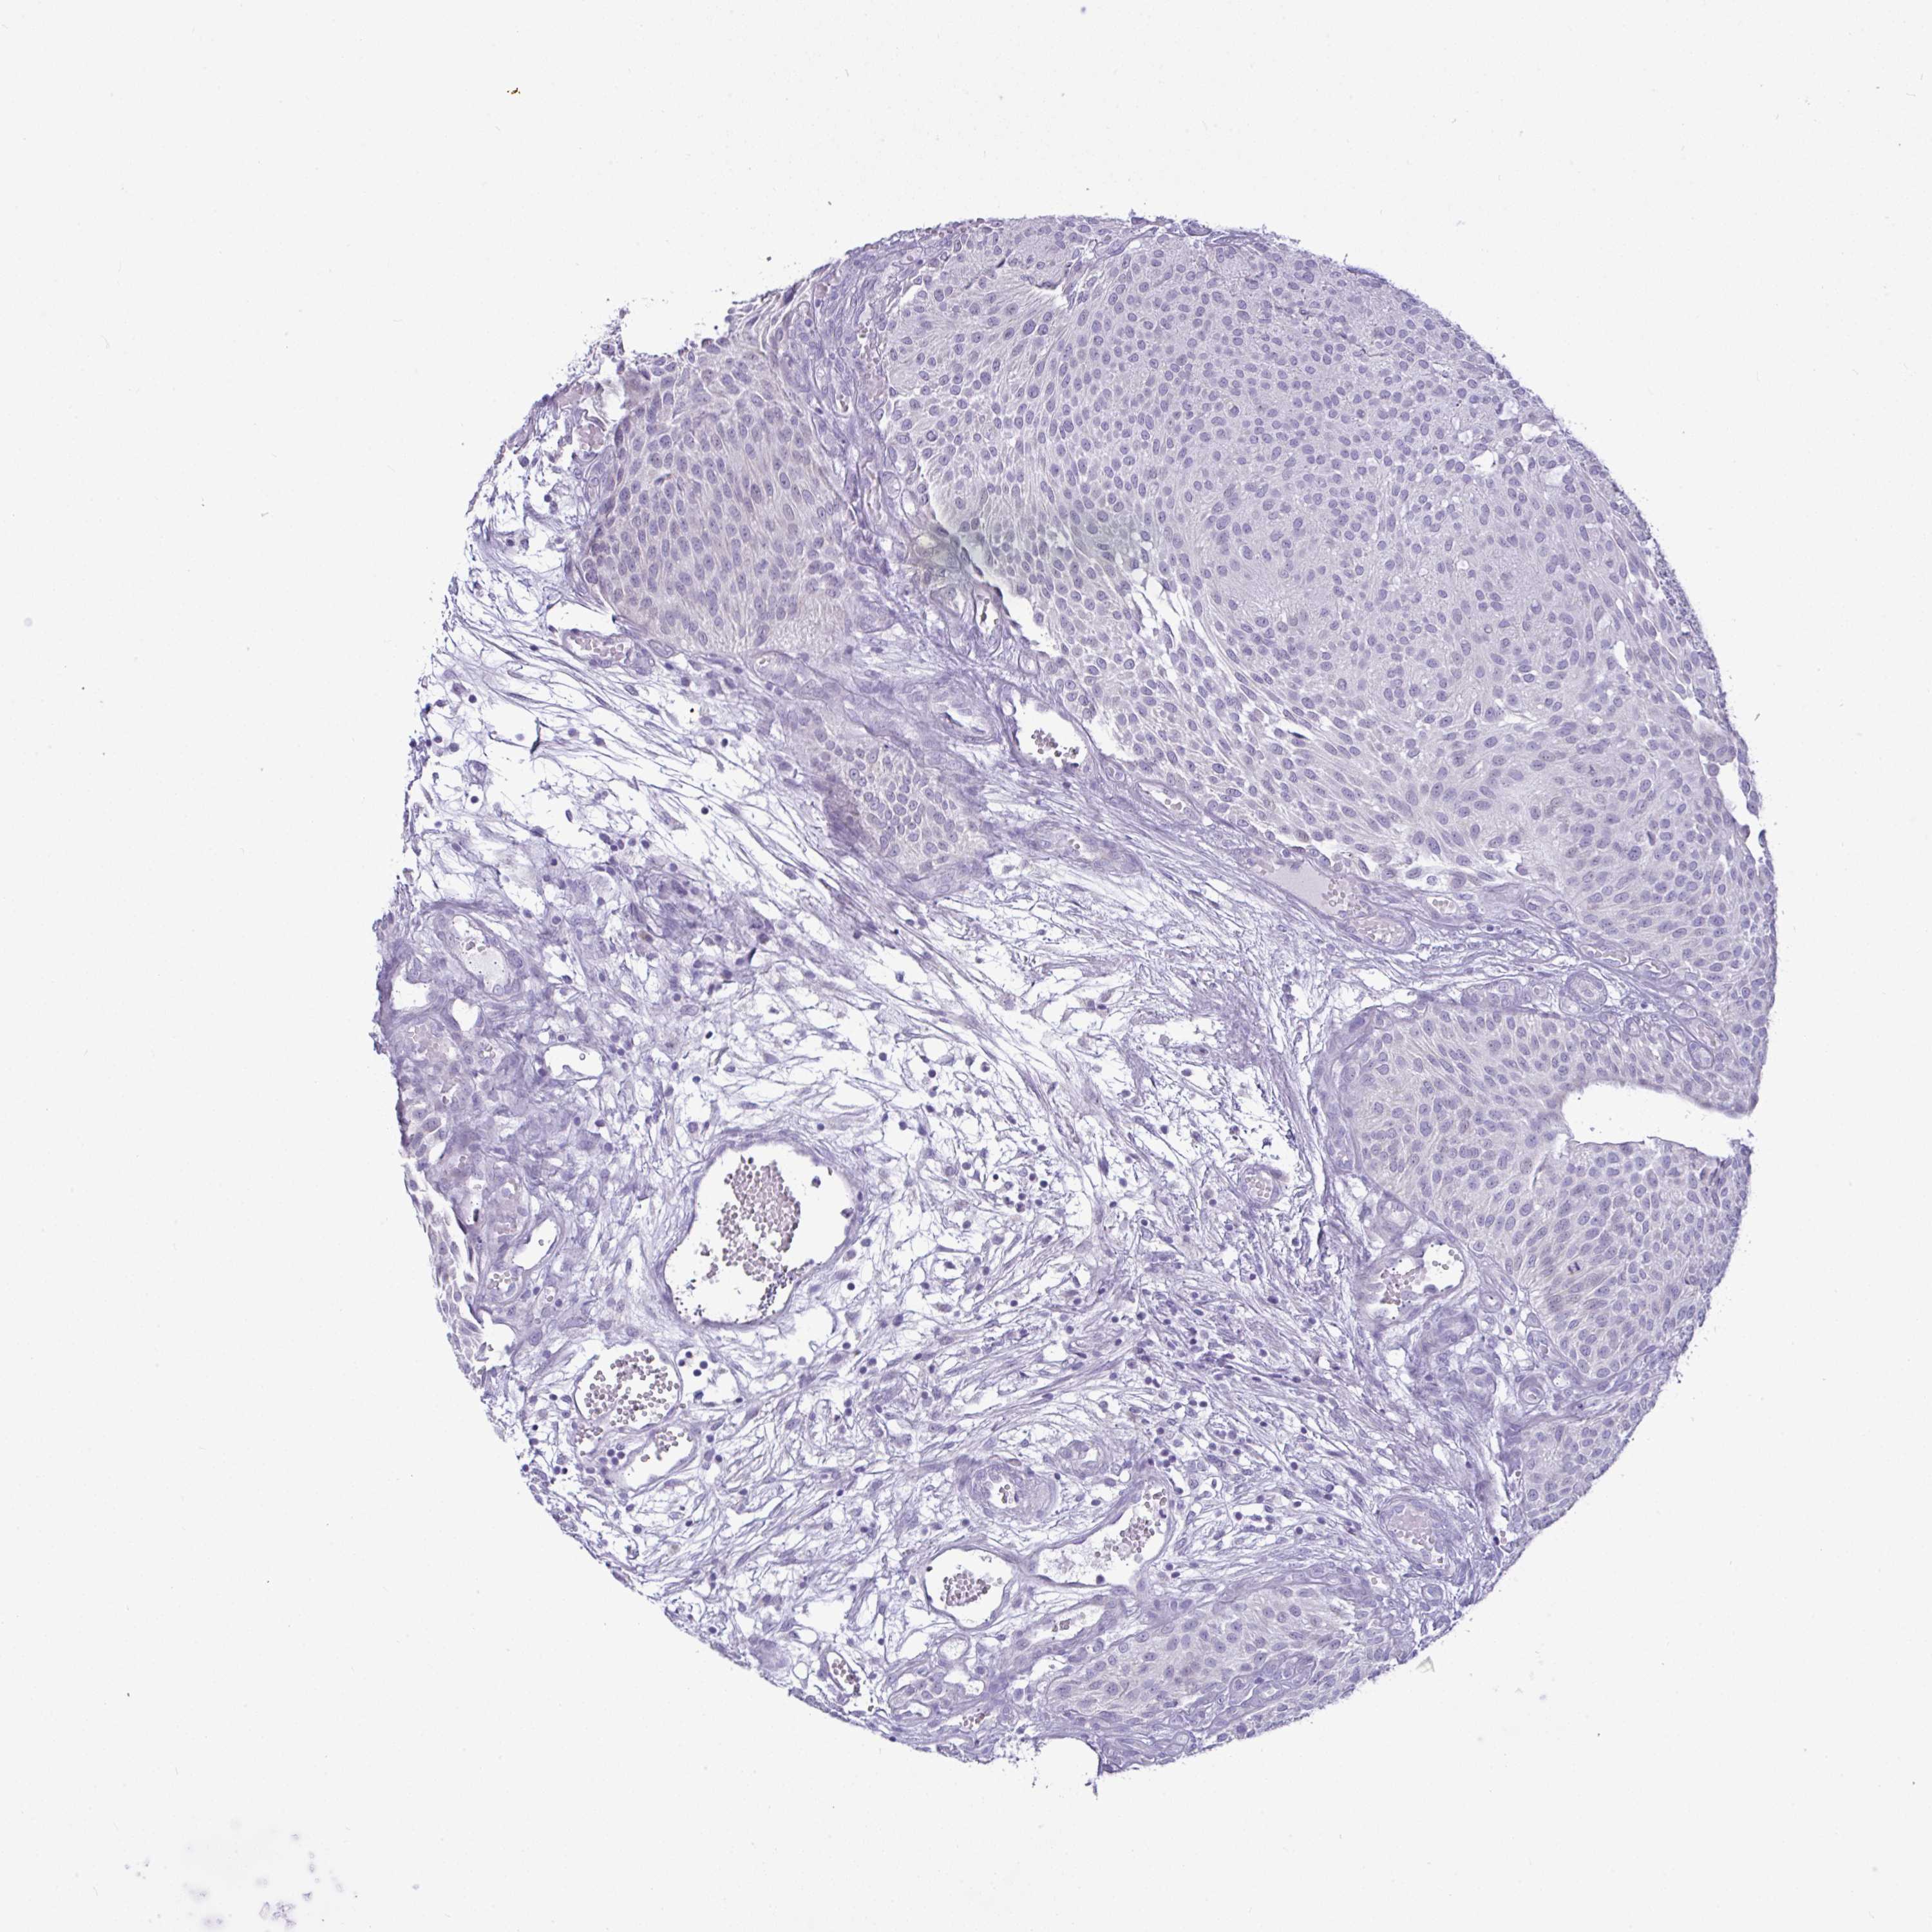

UROTHELIAL CANCER - Protein expressioni

A mouse-over function shows sample information and annotation data. Click on an image to view it in a full screen mode. Samples can be filtered based on level of antibody staining by selecting one or several of the following categories: high, medium, low and not detected. The assay and annotation is described here.

Antibody stainingi

Antibody staining in the annotated cell types in the current human tissue is reported as not detected, low, medium, or high, based on conventional immunohistochemistry profiling in selected tissues. This score is based on the combination of the staining intensity and fraction of stained cells.

Each image is clickable and will lead to virtual microscopy that enables deeper exploration of all samples and also displays staining intensity scores, fraction scores and subcellular localization as well as patient and tissue information for each sample.

Antibody HPA053904

Antibody HPA056744

Antibody CAB012332

Staining

High

Medium

Low

Not detected

Intensity

Strong

Moderate

Weak

Negative

Quantity

>75%

75%-25%

<25%

None

Location

Nuclear

Cytoplasmic/membranous

Cytoplasmic/membranous,nuclear

Urothelial carcinoma, High grade

Urothelial carcinoma, NOS

Urothelial carcinoma, Low grade